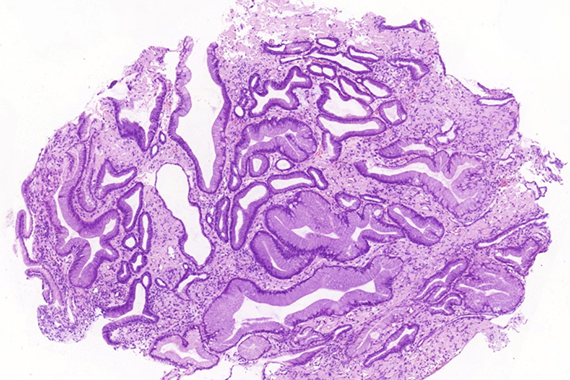

Histologically, lamina propria of gastric mucosa was expanded with amorphous paucicellular stromal deposits with cracking artifacts (Panels A and B). These depositions stained red with Congo Red stain (Panel C) and demonstrated characteristic apple-green birefringence in polarized light (Panel D). No malignancy was observed. Consequently, the final diagnosis was gastric amyloidosis.